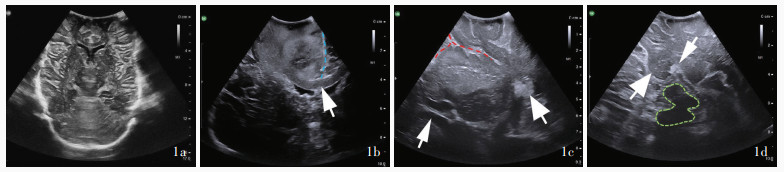

Toma D, Buvala J, Šteňo A. Hyperechoic area under insular gliomas: a potentially hazardous intraoperative ultrasound artifact. World Neurosurg, 2024, 182: e899- e904.

doi: 10.1016/j.wneu.2023.12.086